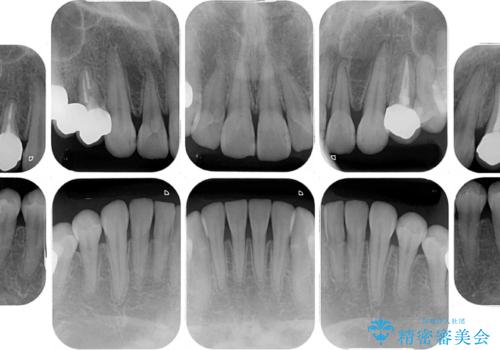

まずはむし歯の治療を行い、その後ワイヤー矯正にて咬み合わせを改善し、途中インプラント埋入を行い、矯正治療後に補綴治療を行うこととしました。

治療の期間と費用はかかりますが、初診時とは比べものにならないほど良好な状態にて治療を終えることができました。